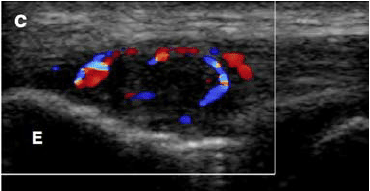

급성기에는

혈관 증식이 나타나기도 하고,

도플러 검사에서 혈류 시그널이 증가되어 있습니다.